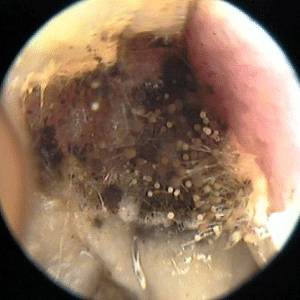

| Эндоскопия носа и пазух | Визуальный осмотр слизистой, выявление грибковых масс. | Позволяет оценить степень поражения и взять материал для анализа. |

Перед тем как назначить необходимое лечение, врач проводит диагностику заболевания. Этот процесс включает не только визуальный осмотр, но и рентгенографию, а также компьютерную томографию.

На основе полученных анализов специалисты определяют тип грибка, вызвавшего воспаление, после чего проводится микологическое исследование.